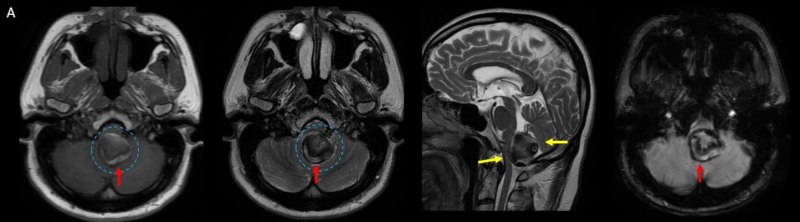

- A. Posterior fossada, T2A, T1A görüntü ve SWAN sekanslarda, 3.5 cm boyutta, düzgün sınırlı, T1A hiperintens, T2A hipointens heterojen iç yapıda kitlesel lezyon izleniyor (çember). Lezyonun serebellum ve kraniyoservikal bileşkeye bası etkisi mevcuttur (ok). Lezyon periferinde T1A, T2A ve SWAN görüntülerde hiperintens tubuler yapı bulunmaktadır (ok). Bu yapı intralezyonel “yılanvari eksantrik vasküler’’ yapıdır.

- B. Kontrastsız BT incelemede heterojen dansitede, perferinde kaba kalsifikasyon gösteren kitle lezyonu (ok), BT anjiografi MIP aksiyal kesitte yılan gibi eksantrik bir açık damar görülmektedir (ok). Sağ posterior inferior serebellar arterden (PICA) doluş gösteren tortiyoze dilate vasküler yapı (ok) DSA’ da demonstre edilmiş.

- MR

- Kısmen tromboze olmuş dev serebral anevrizma, kan ürünlerinin değişken yaşına bağlı olarak MRG’de heterojen bir sinyale sahiptir.

- T1 kısmen tromboze anevrizmada genellikle hiperintens odaklarla heterojen

- T2 kısmen tromboze anevrizmada genellikle hipointens odaklarla heterojen, serpantin anevrizma içi damar kanalında akım boşlukları, bitişik parankimde vazojenik ödem görülebilir.

- T2 ve SWAN genellikle santral-çevresel duyarlılık artefaktları görülür.

- MRA serpantin anevrizma içi damar kanalı iyi gösterir.

- DSA

- Serpantin anevrizmaların tanısında altın standart olarak kabul edilir.

- Anevrizmanın şeklini, giriş ve çıkış noktalarınıen net şekilde gösterir.

- DSA’da anevrizma içindeki tortuöz damar kanalının morfolojisi, bir simite (“pretzel işareti”) benzetilmiştir. Bu bulgu, anevrizmanın dinamik yapısını ve içindeki kan akışınıgörselleştirmek için kritik bir bulgudur.